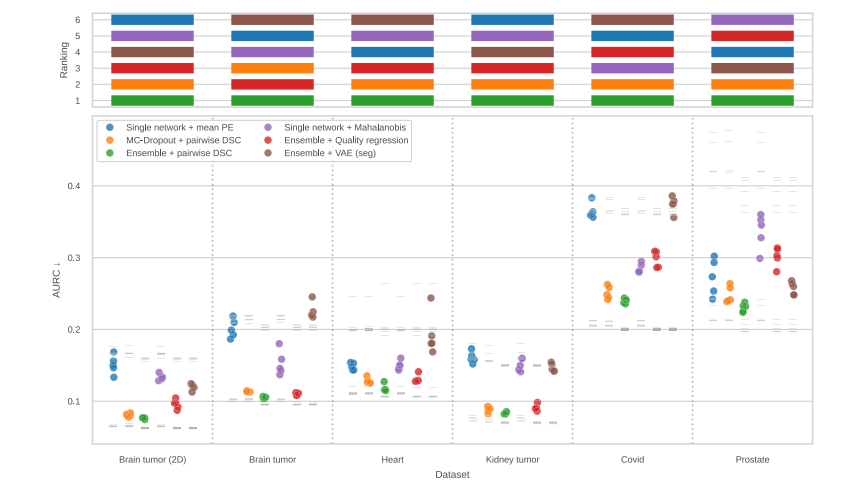

Fig. 4. Rankings by average AURC (top, lower ranks are better) and the underlying AURC scores (bottom; lower is better) for methods from Section 4.4.3 and all datasets. Theexperiments are named as ‘‘prediction model + confidence method’’ and each of them was repeated using 5 folds. In the lower diagram, colored dots denote AURC values achievedby the methods, while gray marks above/below them are AURC values for random/optimal confidence rankings (which differ between the models trained on different folds; seeSection 4.1). Ensemble + pairwise DSC is the best method overall, often achieving close to optimal AURC scores. The ranking on the prostate dataset is an outlier, which couldbe due to the small training set size. PE: predictive entropy

图4. 按照平均AURC排名(上图,排名越低越好)以及基础AURC得分(下图,得分越低越好)对第4.4.3节中的方法进行排名,涵盖所有数据集。实验名称为“预测模型 + 置信度方法”,每个实验使用5折交叉验证重复进行。在下图中,彩色点表示方法所达到的AURC值,而其上方/下方的灰色标记表示随机/最优置信度排名的AURC值(这些值在不同折次训练的模型之间有所不同;见第4.1节)。集成+成对DSC是整体表现最好的方法,通常能接近最优的AURC得分。前列腺数据集的排名为异常值,可能是由于训练集较小的缘故。PE:预测熵

In conclusion, our study addresses the pitfalls in existing evaluation protocols for segmentation failure detection by proposing aflexible evaluation pipeline based on a risk-coverage analysis. Usingthis pipeline, we introduced a benchmark comprising multiple radiological 3D datasets to assess the generalization of many failure detectionmethods, and found that the pairwise Dice score between ensemblepredictions consistently outperforms other methods, serving as a strongbaseline for future studies.

总之,我们的研究通过提出一个基于风险覆盖分析的灵活评估管道,解决了现有分割失败检测评估协议中的不足。通过使用这个评估管道,我们引入了一个包含多个放射学3D数据集的基准,评估了多种失败检测方法的泛化能力,并发现集成预测之间的成对Dice分数始终优于其他方法,成为未来研究的强有力基准。